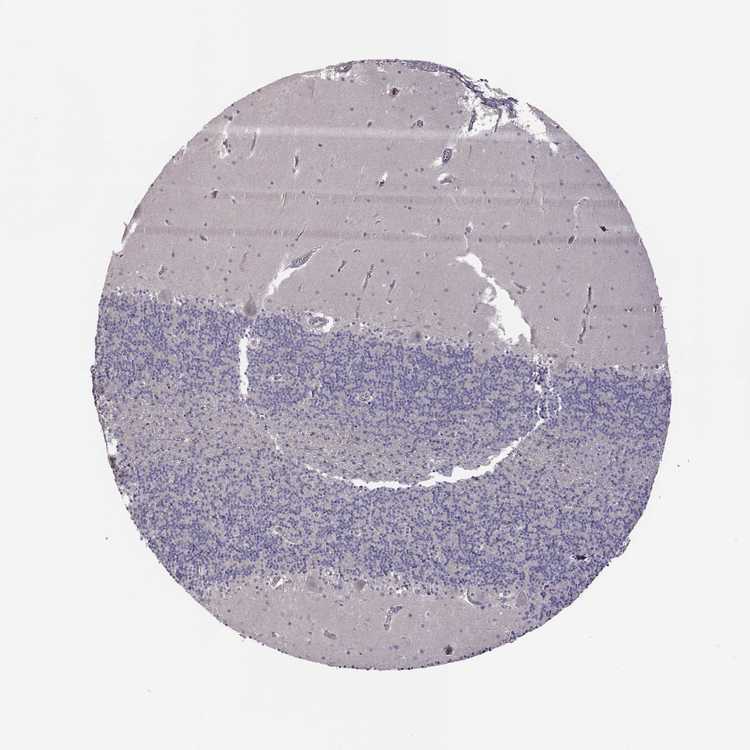

CEREBELLUM - Antibody stainingi

Antibody staining in the annotated cell types in the current human tissue is reported as not detected, low, medium, or high, based on conventional immunohistochemistry profiling in selected tissues. This score is based on the combination of the staining intensity and fraction of stained cells.

Each image is clickable and will lead to virtual microscopy that enables deeper exploration of all samples and also displays staining intensity scores, fraction scores and subcellular localization as well as patient and tissue information for each sample.

Antibody HPA031115Antibody HPA056942

Purkinje cells Not detectedNot detected

Cells in granular layer Not detectedNot detected

Cells in molecular layer LowNot detected